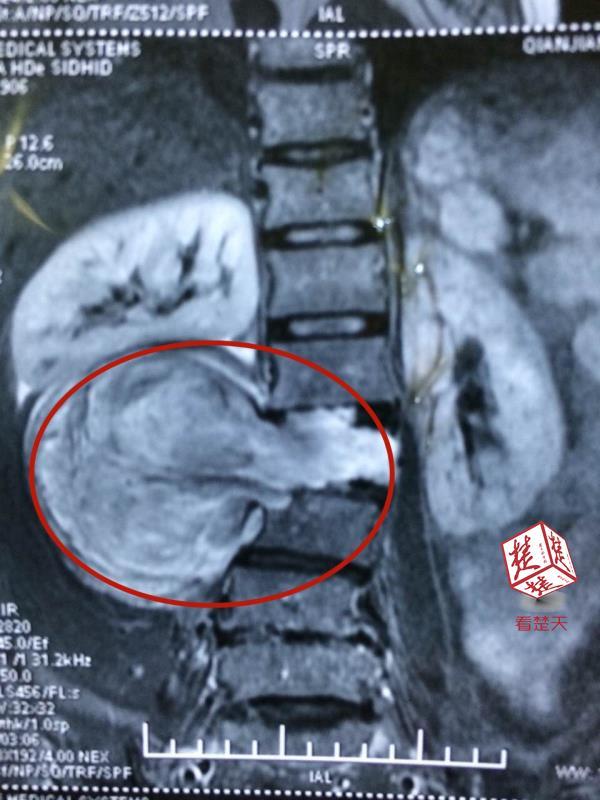

在他腰椎管藏下隐形炸弹,医生巧摘肿瘤

552x481 - 25KB - JPEG